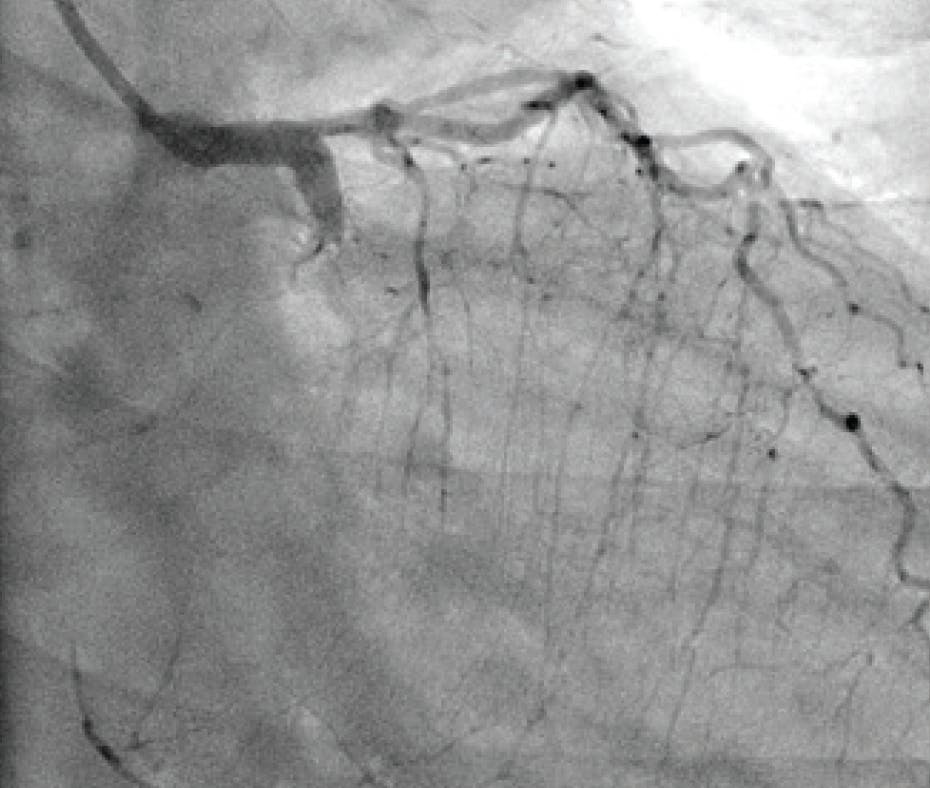

Figure 1. Initial angiogram of the left lobe.

INTERVENTION

After achieving wire access, the Lightning Flash 2.0 was inserted. While in “Gallop Mode,” the saddle clot burden and subsequently the left and right main PAs were aspirated. Once the algorithm returned to “Sampling Mode,” aspiration was turned off and angiograms were obtained to assess the progress. After 5 minutes of aspiration, reperfusion of the main PAs and distal branches was achieved (Figure 3, Figure 4, and Figure 5), with improvement in the patient’s vital signs and no device-related complications.

Figure 3. Postthrombectomy angiogram of the left lobe.